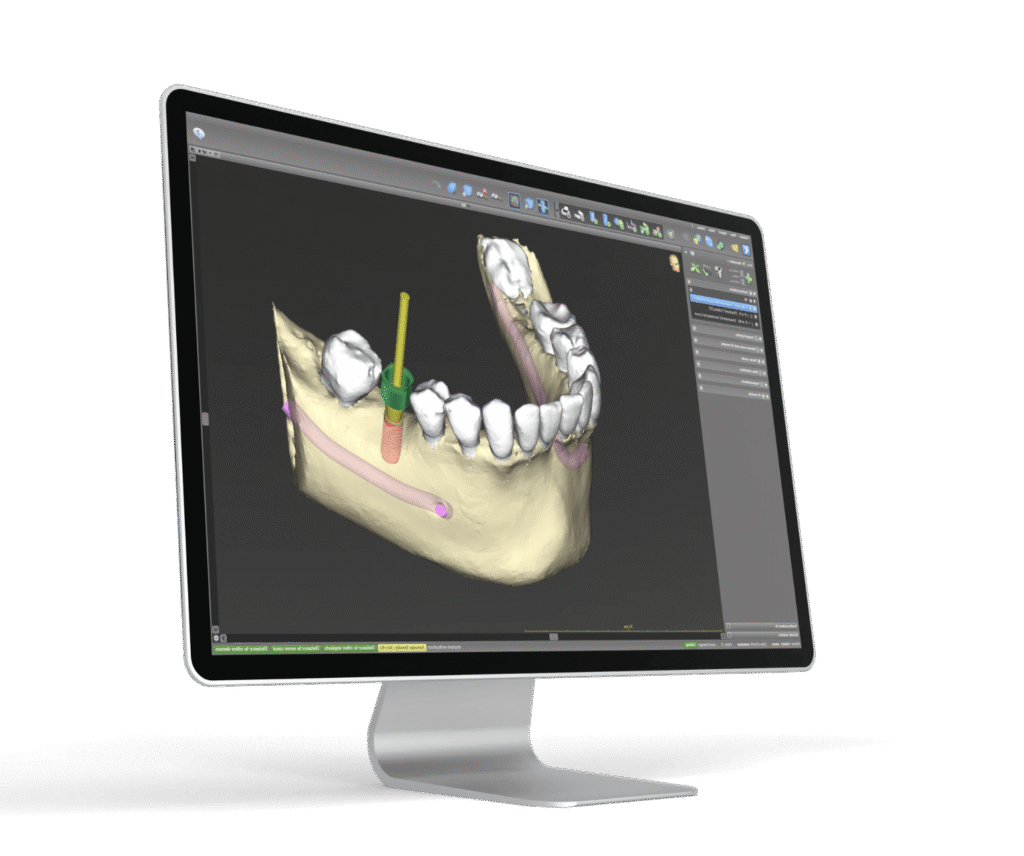

CHIRURGIA IMPLANTARE COMPUTER- GUIDATA: Mininvasività, Accuratezza e Prevedibilità

Tecnica avanzata che utilizza la tecnologia digitale per pianificare esattamente la posizione, l’angolazione e la profondità dell’impianto in base alle condizioni anatomiche individuali ed in modo preciso e minimamente invasivo.

Si utilizzano radiografie 3D (come la CBCT) per ottenere una visione dettagliata della struttura ossea e dei tessuti molli del pazienti. Il modello digitale viene importato da software specializzati che generano un template chirurgico (una guida personalizzata), che viene utilizzata durante l’intervento per garantire che l’impianto venga inserito con precisione millimetrica, riducendo il rischio di complicazioni , quali danni a nervi e strutture vitali, e migliorando l’efficacia del trattamento.